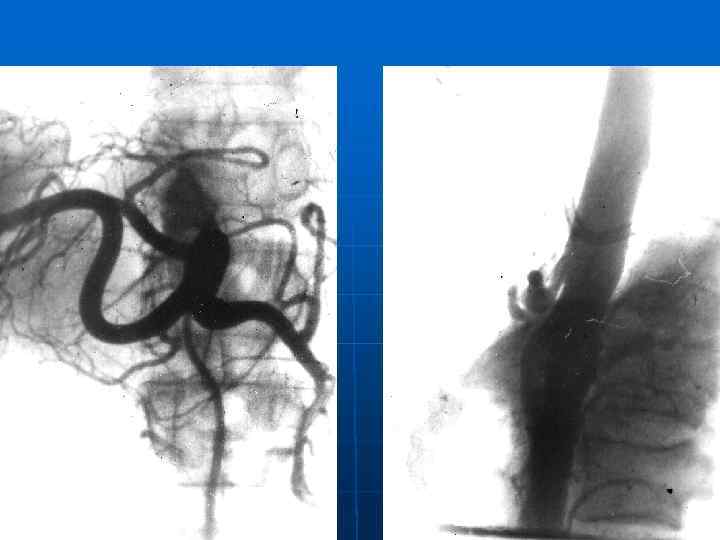

Диагностика: -болевой синдром при отсутствие органической патологии со стороны органов брюшной полости (желудок и ПЖ) -КТ и УЗИ подж. жел. -ФГДС желудка, рентгеноскопия желудка. -Шум над чревным стволом (ЭКЧС) -Дуплекс чревного ствола на вдохе и выдохе (на выдохе увеличение скорости кровотока, завихрение потока) -Целиакография и аортография в боковой проекции (ЭКЧС) -Электростимуляция чревного сплетения (катетеризация ЧПЗ с блоком медикаментозным)